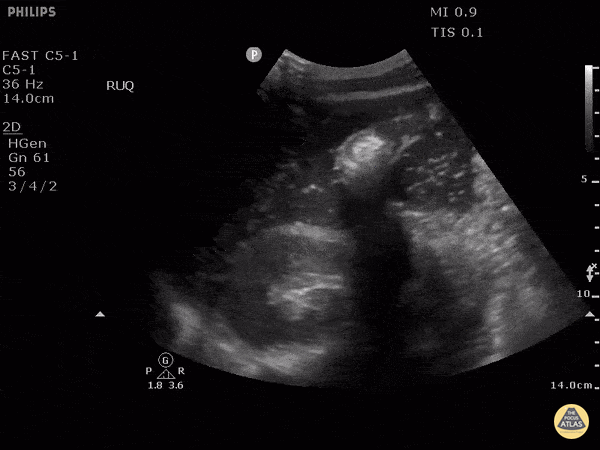

Patient presented with altered mental status, hypotension and a rigid abdomen. It was unclear at the time if this patient’s presentation was due to trauma. Right-upper quadrant ultrasound used to view for potential cause using the perihepatic window. Here we can see air within fluid and a hyperechoic peritoneal stripe, indicating a perforated viscus. In this case, due to a duodenal ulcer. Image courtesy of Robert Jones DO, FACEP @RJonesSonoEM Director, Emergency Ultrasound; MetroHealth Medical Center; Professor, Case Western Reserve Medical School, Cleveland, OH View his original post here